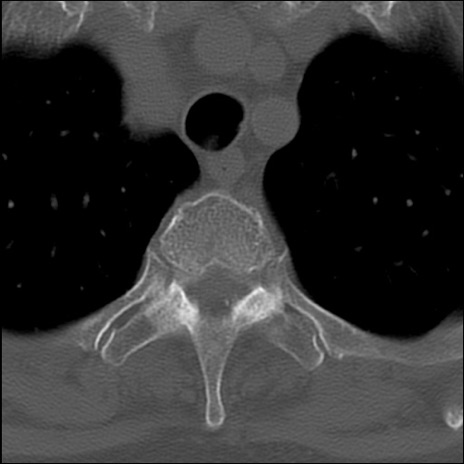

症例48 頚椎CT(横断像)

頚椎CT